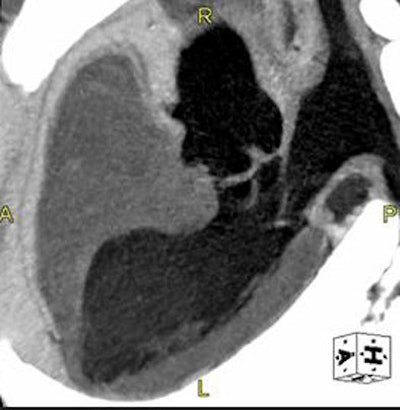

| Biphasic contrast injection offers more even enhancement of the coronary arteries. Images courtesy of Dr. Dominik Fleishchmann. |

Biphasic or multiphasic injection capabilities are standard on most power injectors today. They can modulate contrast flow during the course of injection. The main utility is aortic enhancement, which cannot be achieved with a uniphasic injection, Fleischmann said.

"If you use first a high-injection flow rate for the first five to six seconds like a surge phase to get the contrast up at the beginning, then you continue with a lower flow rate, you will get a plateau-like enhancement," he said. For injection durations 30 seconds and longer, biphasic injection produces much more homogeneous opacification over time.

But biphasic injections don't produce the best possible enhancement curves. Abrupt chances in contrast flow from biphasic injections can be plotted on a distinctly unflat "camelback-shaped curve," Fleischmann said. Multiphasic injection is the way to achieve a longer, smoother plateau, he said.